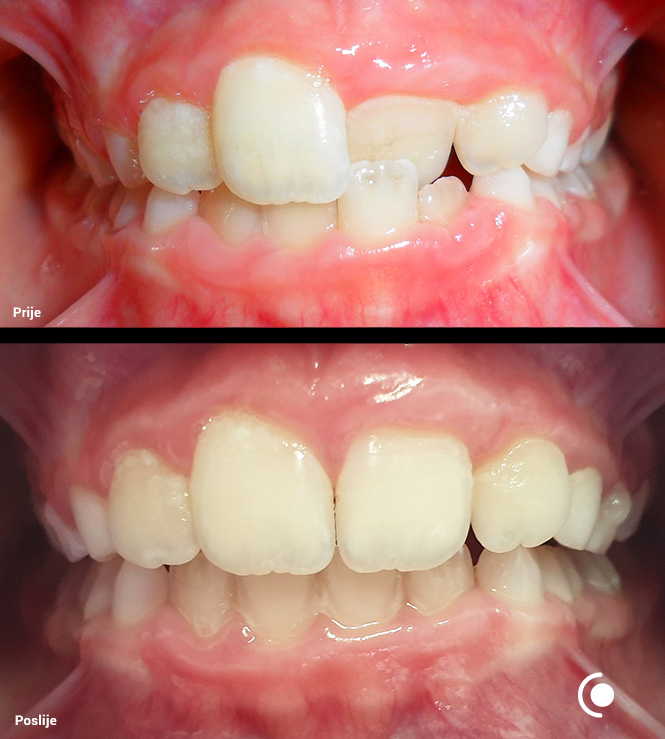

O našoj kvaliteti najbolje govore naši rezultati!